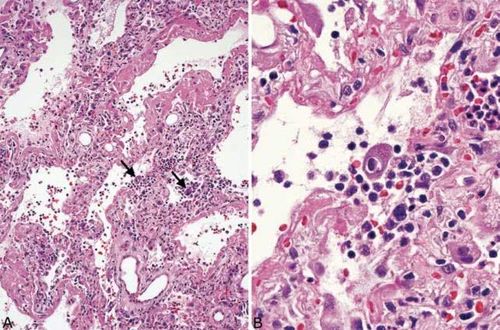

病毒性肺炎切片

病毒性肺炎切片,病毒性肺炎

从病理学角度认识并了解病毒性肺炎